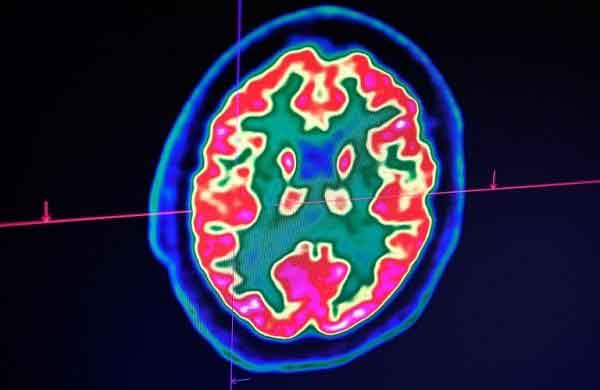

Bị COVID-19 nặng có thể tổn thương não

Một nghiên cứu sơ bộ tại Anh phát hiện COVID-19 gây ra tổn thương não, dẫn đến biến chứng như đột quỵ, viêm, rối loạn tâm thần và vài triệu chứng giống mất trí nhớ ở trường hợp bệnh nặng. Tin, bài liên quan: Rút ngắn thời gian điều trị COVID-19 bằng cách dùng kết hợp ba loại thuốc